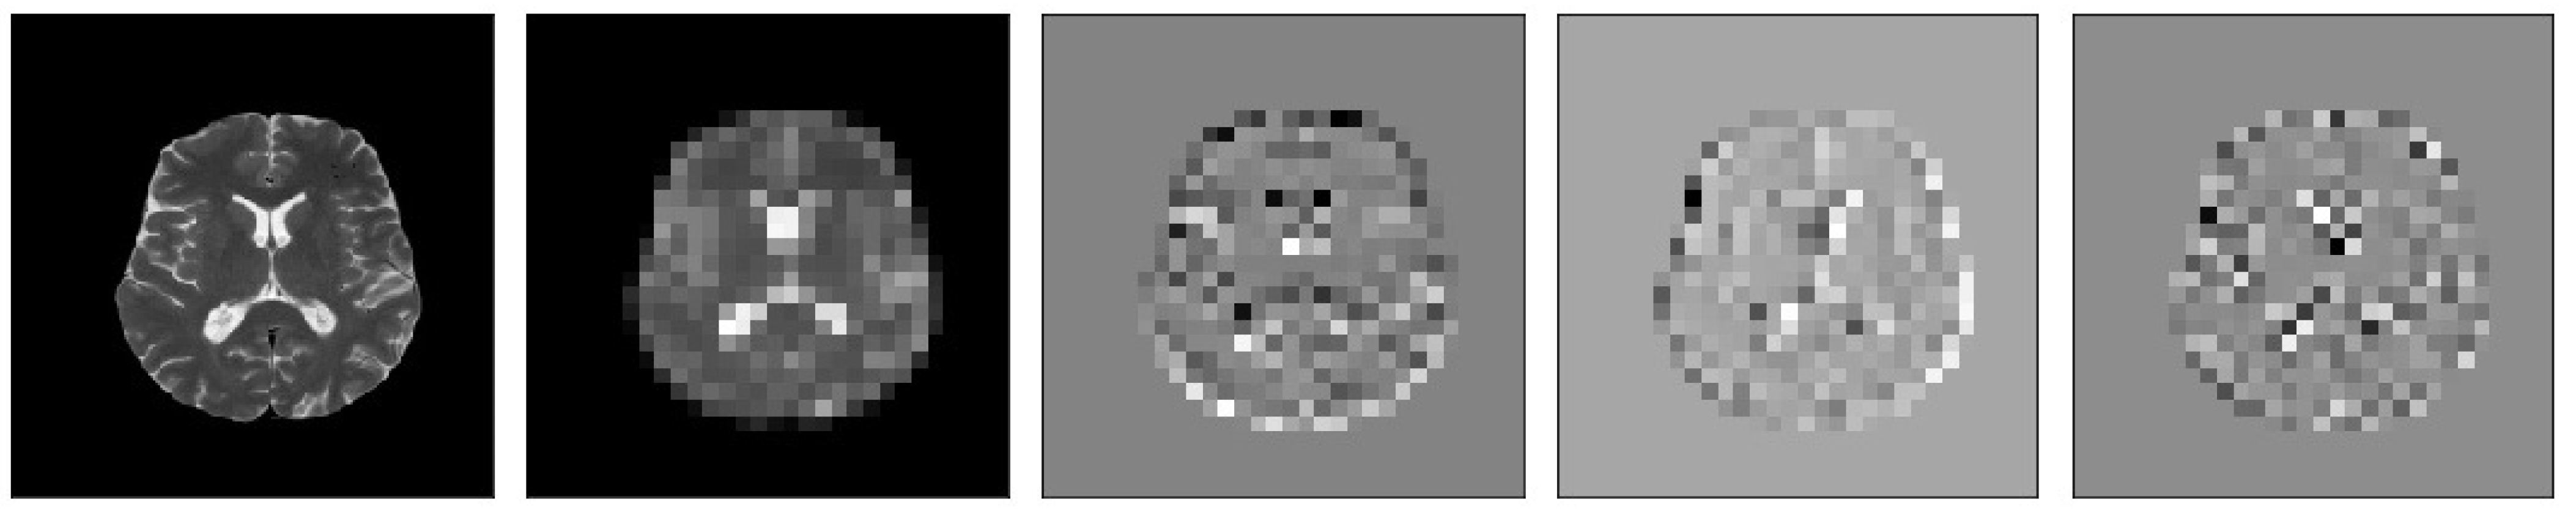

Figure 5.

Samples of our Level 1 DWT decomposition of a non-healthy MR image type T2.

Figure 6.

Samples of our Level 2 DWT decomposition of a non-healthy MR image type T2.

Figure 7.

Samples of our Level 3 DWT decomposition of a non-healthy MR image type T2.

Figure 8.

Samples of our Level 1 DWT decomposition of a healthy MR image type T2.

Figure 9.

Samples of our Level 2 DWT decomposition of a healthy MR image type T2.

Figure 10.

Samples of our Level 3 DWT decomposition of a healthy MR image type T2.